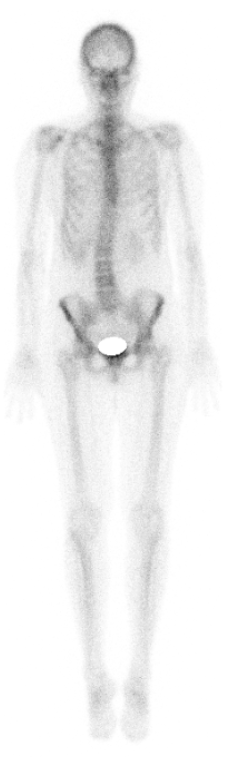

In der Schilddrüsensprechstunde werden Sie bei einer Erstvorstellung umfassend diagnostiziert (Gespräch, Untersuchung, Blutentnahme, Ultraschall und bei Bedarf Szintigraphie), beraten und ggf. therapiert.